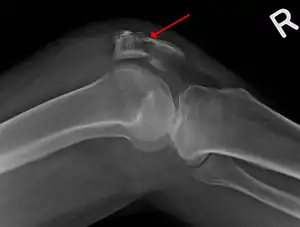

A fracture of the patella seen on a lateral view

Diagnostic methodBased on symptom, confirmed with X-rays.[3]

It typically results from a hard blow to the front of the knee or falling on the knee.[1] Occasionally it may occur from a strong contraction of the thigh muscles.[1] Diagnosis is based on symptoms and confirmed with X-rays.[3] In children an MRI may be required.[3]

Diagnosis is based on symptoms and examination, which typically reveals a swollen knee with reduced movement and a tender kneecap.[5] A fracture is subsequently confirmed with X-rays usually taken from different angles.[3] In children an MRI may be required.[3]